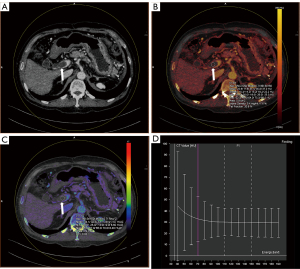

In the ROC analysis (Table 3), the areas under the ROC curves (AUC) for differentiating neoplastic from bland PVT were 0.963, 0.970, and 0.969 for IC, NIC-A, and NIC-V, respectively; and 0.732, 0.952, 0.949, and 0.933 for Rho, Z, DEI, and K, respectively (Figure 4). When the cut-off value for IC was set at 0.950 mg/mL, the diagnostic performance achieved a sensitivity of 96.0% and a specificity of 97.0%. At cut-off values of 19.2% for NIC-A and 24.3% for NIC-V, the diagnostic performance demonstrated sensitivities of 93.2% and 97.3%, and specificities of 96.0% and 91.9%, respectively. When the cut-off values for Rho and Z were set at 37.9 e−/cm3 and 8.05 respectively, the diagnostic performance yielded sensitivities of 68.9% and 96.0% and specificities of 69.7% and 89.9%, respectively. At cut-off values of 0.011 for DEI and 1.10 for K, the diagnostic performance showed sensitivities of 96.0% and 90.5%, and specificities of 87.9% and 88.9%, respectively. Examples of both bland and neoplastic PVT are illustrated in Figures 5,6.